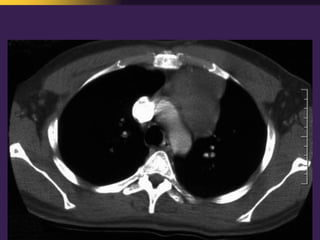

This document discusses mediastinal pathology using a compartmental approach. It describes the anatomy of the mediastinum and divides it into anterior, middle, and posterior compartments. Each compartment contains different structures and has a characteristic distribution of lesions. For example, 50% of lesions occur in the anterior compartment, which contains the thymus. The thymus is the most common site of lesions in the anterior compartment. Thymomas are the most common epithelial tumors of the thymus and mediastinum.